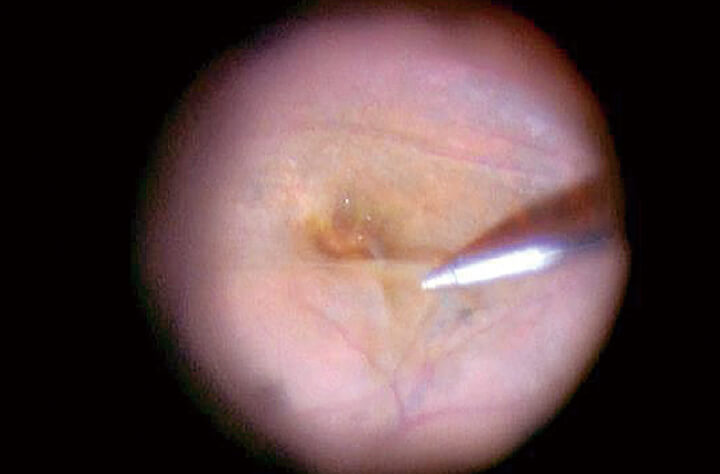

Even during ultrasonic phacoemulsification and aspiration (PEA), which can weaken the red reflex illumination, the lens can be seen clearly due to the bright red reflex illumination.

Sufficient red reflex illumination can also be obtained for small pupils. In addition, bright and stable red reflex illumination can always be obtained, even when the direction of the eye changes.

Using only red reflex illumination produces high contrast, enhanced images of the lens.